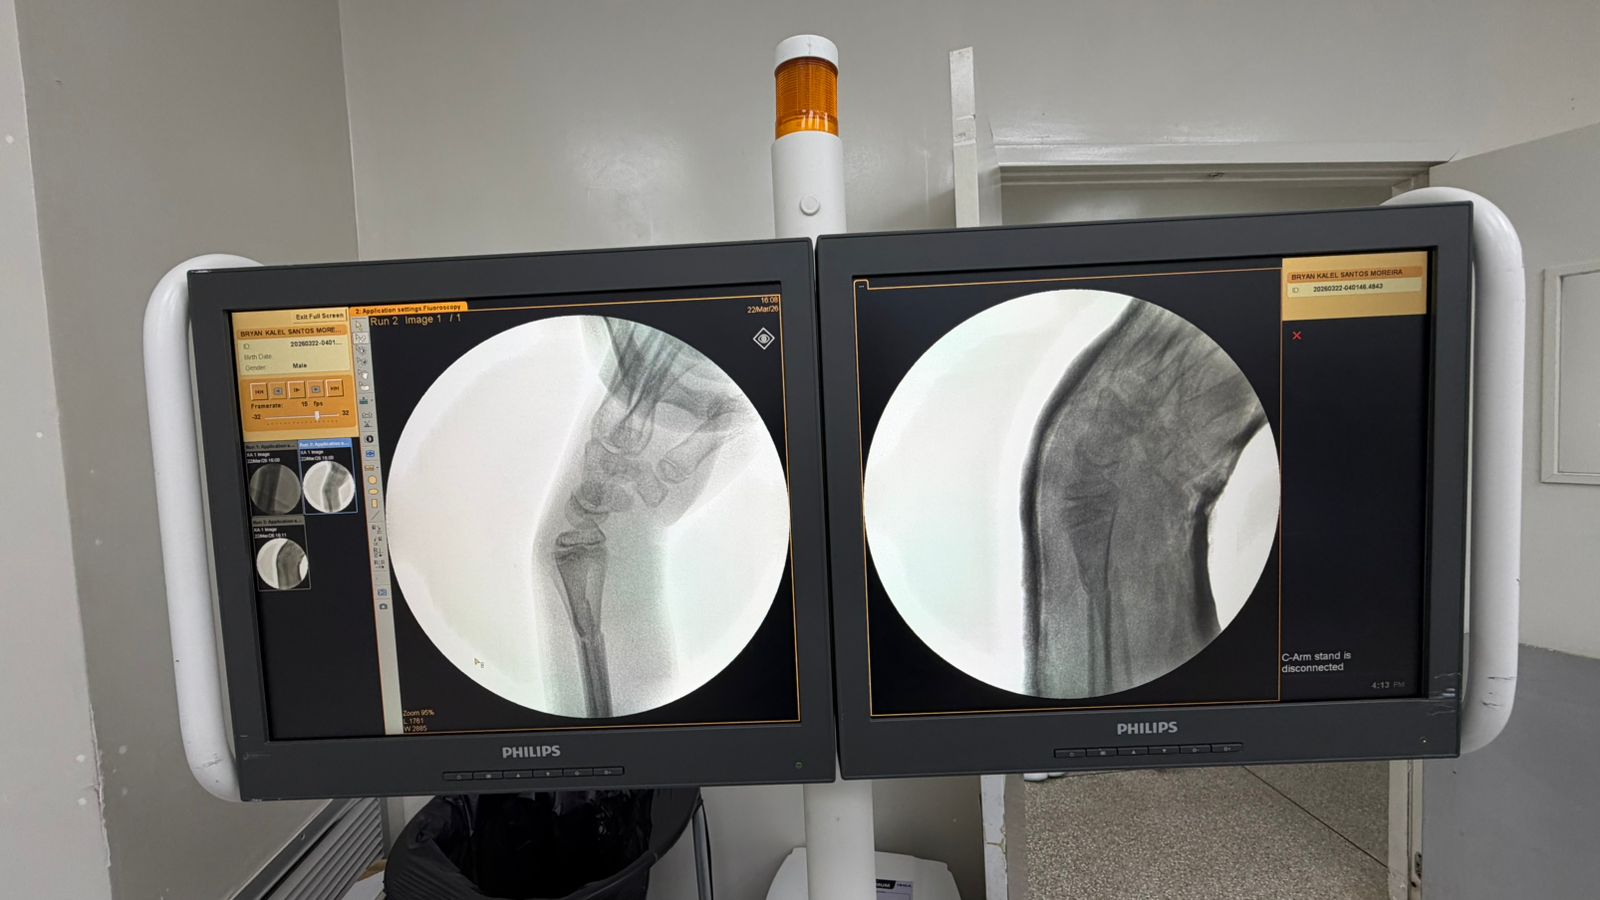

Essa transformação não está apenas nos números. Ela pode ser vista. As imagens que acompanham este texto mostram dois casos atendidos hoje no pronto socorro: crianças com fraturas no antebraço que foram avaliadas, diagnosticadas e operadas no próprio hospital, sem necessidade de transferência. Situações que exigem agilidade, equipe treinada e estrutura funcional.

Em outro episódio recente, uma criança em férias na cidade, com fratura grave de cotovelo, passou por todo o processo, do atendimento à alta hospitalar, em cerca de 10 horas, e já recuperada enviou um vídeo de agradecimento diretamente de Portugal, há dois dias.